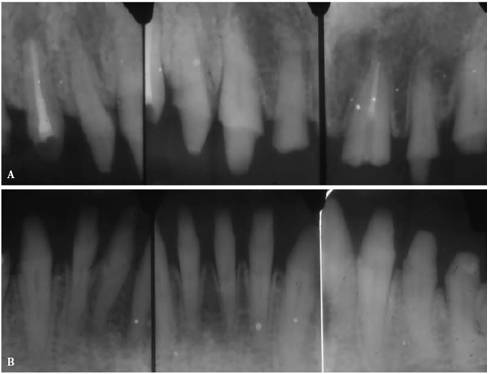

Reconstructive planning requires a full set of well-angulated long cone-exposed

films or digital images using film holders like XCP (DENTSPLY/Rinn, Elgin, IL),

which enables 90-degree angulation of the x-ray beam on the film or sensor. In

addition to a good angulation on the radiograph, these film holders will enable

the operator to take comparable films or digital images over time, which is

very important when evaluating healing or failure.

When dealing with extensive cases, panoramic film is equally essential. If the

patient requires endodontic therapy and is referred for treatment, these films

and a description of the goals and objectives of the referring dentist should

be sent to the endodontist prior to the patient's first appointment. Most

endodontists will take additional films of the teeth to be treated to establish

a complete record of their own.

Precementation Radiographs

Prior to cementation, Yamada (personal communication, 2001) re-radiographs the

prepared teeth (Figures 19-25A

and B).

These images check the pulpal, periapical, and periodontal status of the teeth.

Also, the radiographs, unencumbered by the presence of the metal castings,

provide a chamber/canal road map record if the tooth requires endodontics in

the future. This may appear pessimistic, but Arens and Chivian reported that

over 40% of teeth requiring root canal therapy are crowned.4 Prior

knowledge of the size, location, and direction of the chamber and the canal will

reduce the possibility of (1) crown damage during access opening, (2) lost time

searching for the canal orifice, (3) perforations of the chamber or the canal

because of disorientation, (4) natural core elimination by gutting, (5) crown

dislodgment, and (6) sufficient destruction to alter the situation and require

corrective surgery. Each of these iatrogenic possibilities reduces the

prognosis and jeopardizes the tooth's reliability as an abutment.

Figure 19-25A and B: Precementation radiographs provide a road map to the canals if endodontic therapy is necessary after cementation of the castings. (Radiographs courtesy of Dr. Henry Yamada.)